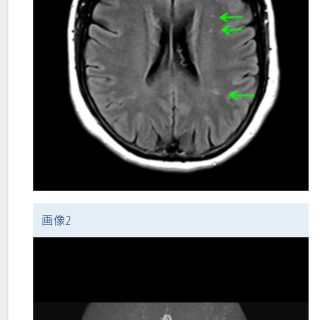

つぶやき、と 日常の、etc / 健康&ダイエット / 暮らしの愉しみ 2024年6月1日 by つくね。 · Published 2024年6月1日 スマート脳ドック 急に思い立って 脳ドックに行ってきた。 その勢いが自分でも不...

つぶやき、と 日常の、etc / 健康&ダイエット 2024年4月23日 by つくね。 · Published 2024年4月23日 脳ドックに行ってくる 片頭痛はずっと。 学生の時から。 だから 頭が痛いからといっ...